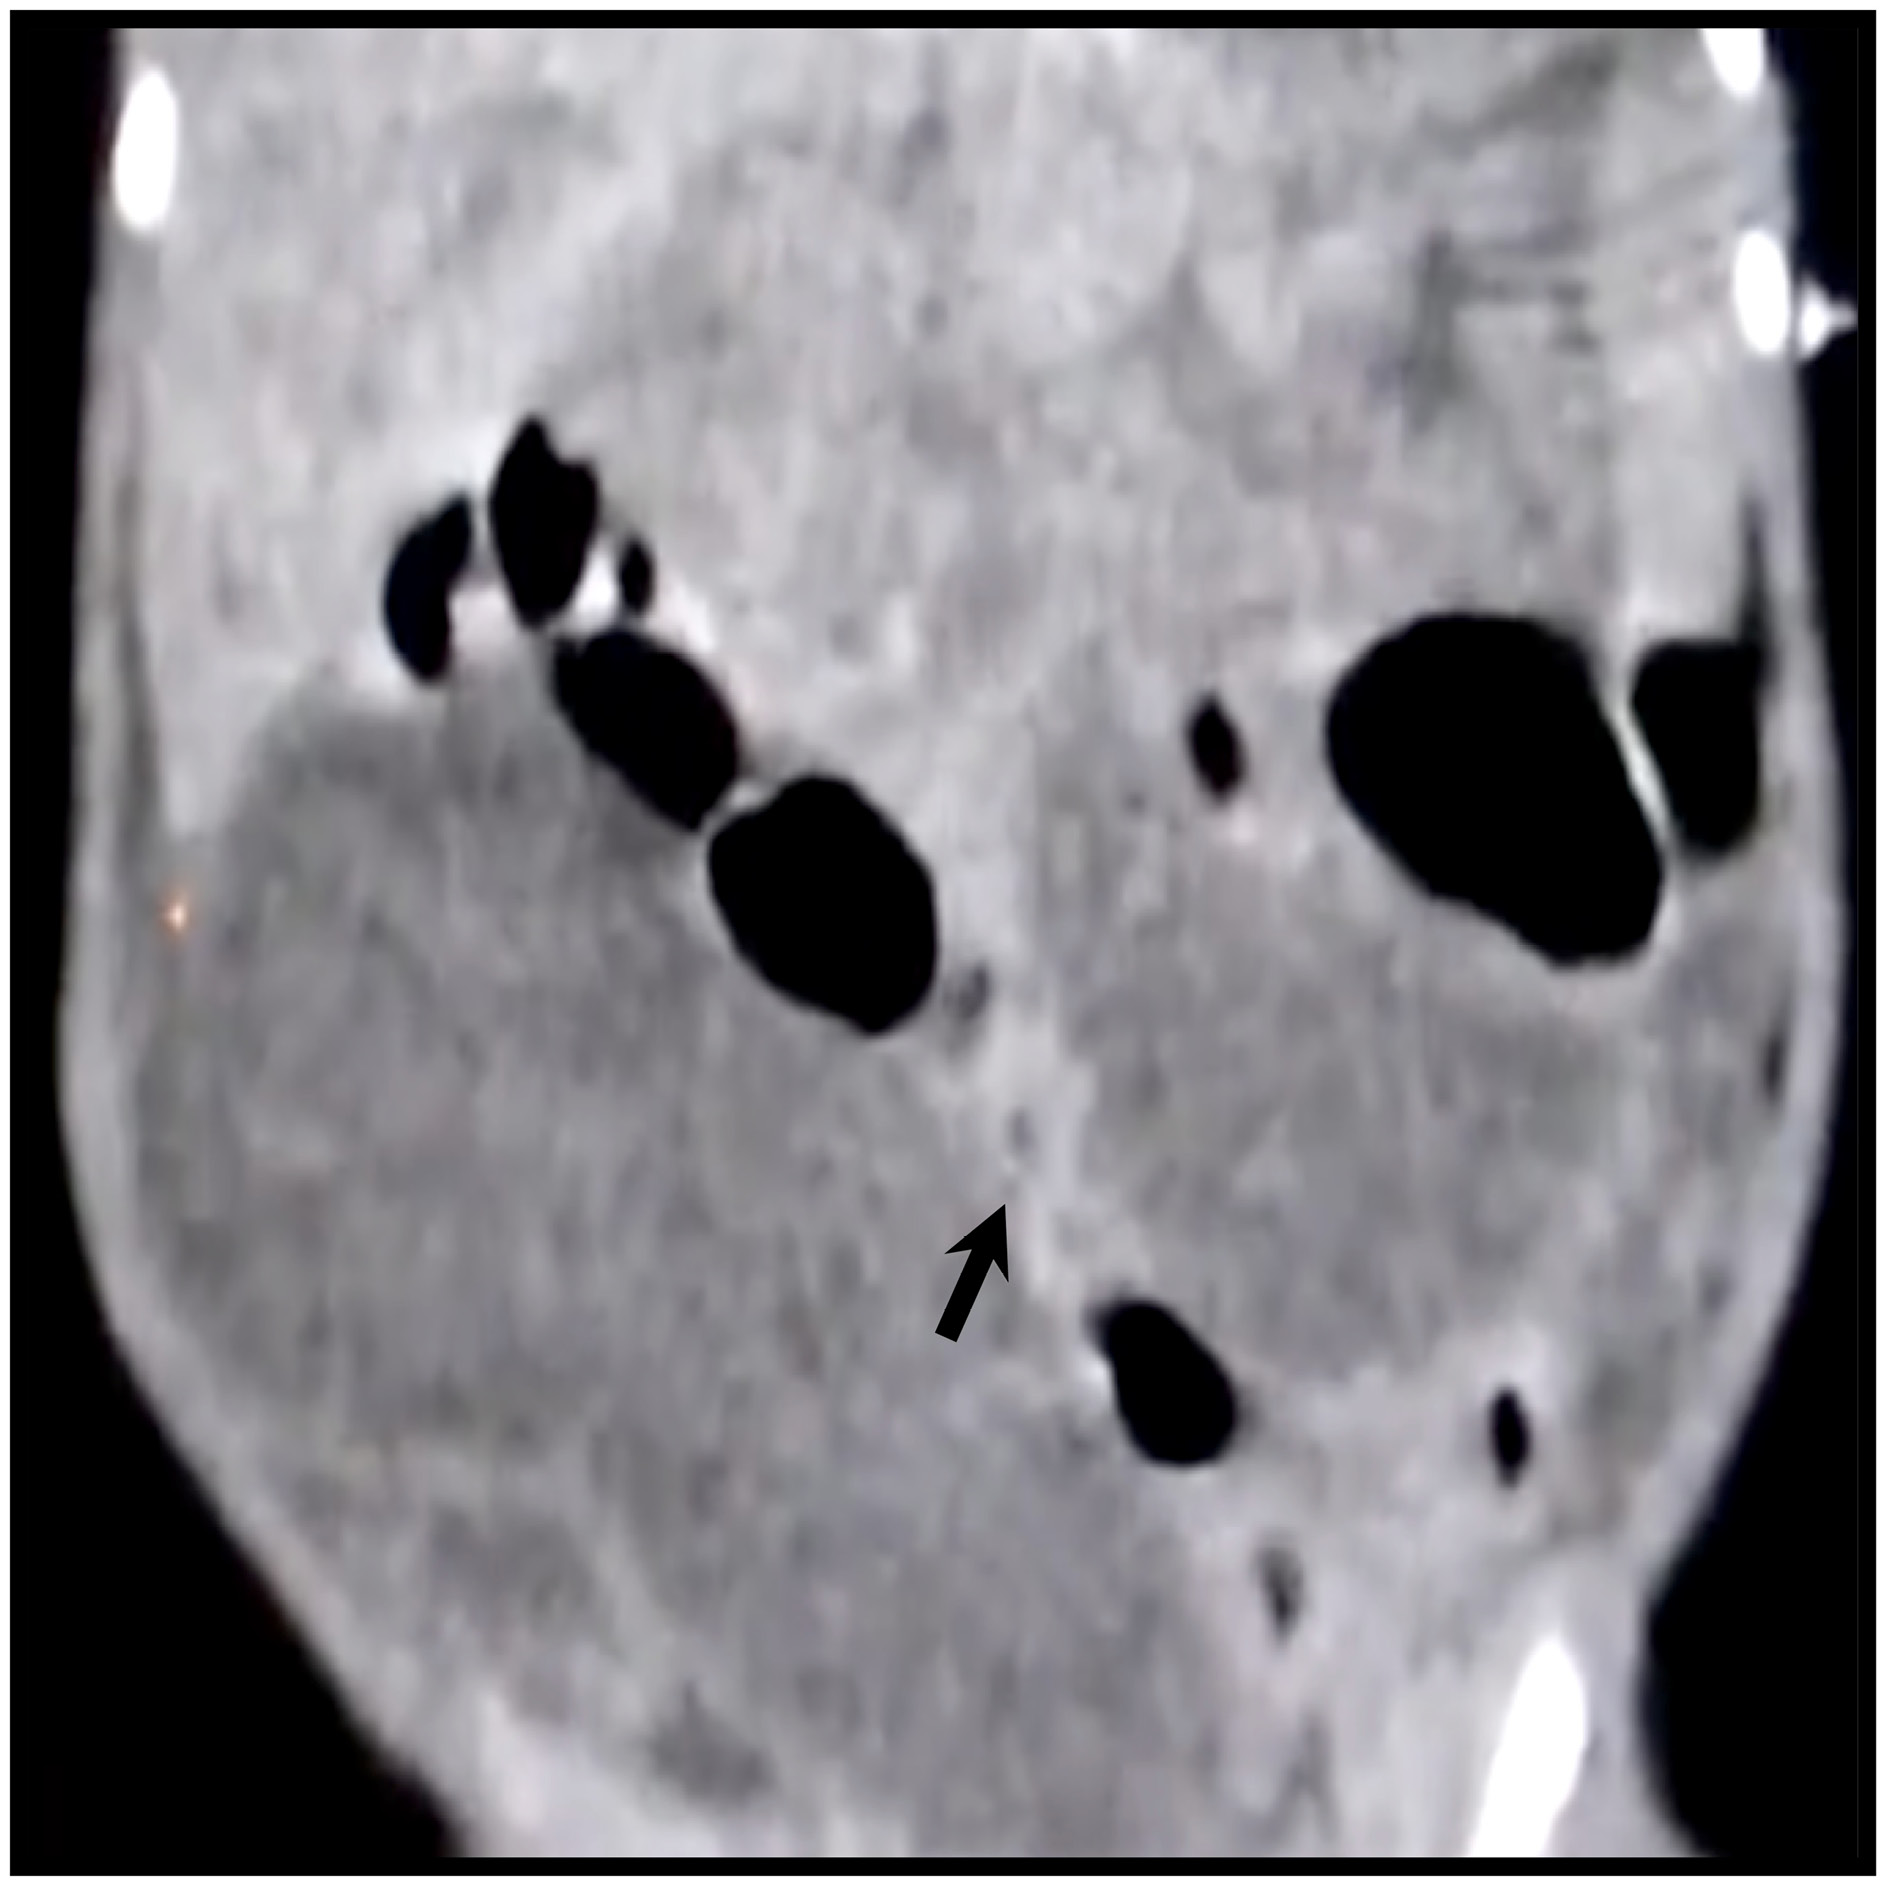

RN masculino de 2 días de vida, prematuro tardío producto de la G:1, madre de 21 años, prenatal 5/9, infección de vías urinarias en el tercer trimestre y cervicovaginitis repetitivas, cultivo de exudado vaginal positivo a Garderella vaginalis y urocultivo positivo a Staphilococcus hominis sin tratamiento. Se obtiene producto por eutocia con peso de 2700gr, talla 51 cm, Apgar 9/9 y prueba de Silverman Anderson: 0, egresado de alojamiento conjunto. Ingresa al servicio de urgencias con cuadro caracterizado por irritabilidad, febril, distensión abdominal, dibujo de asas intestinales y constipación de dos días de evolución. A la exploración física el paciente se muestra febril, irritable, con deshidratación leve, distensión abdominal importante, dibujo de asas, dolor a la palpación superficial, peristalsis disminuida, percusión timpánica y se tomó temperatura rectal con resistencia a la introducción. Los estudios complementarios de hemograma con reporte de leucocitosis, neutrofilia, eosinofilia y monocitosis. La ecografía abdominal mostró hidronefrosis bilateral, íleo reflejo, escaso liquido libre en espacio de Morrison y asas intestinales muy dilatadas. En el estudio radiológico se aprecia mala distribución de aire, pero no se observa dilatación intestinal ni se aprecia imagen de atresia duodenal. En la Tomografía Computada (TC) se observa importante dilatación de asas del intestino delgado (Figura 1).

Figura 1

Reconstrucción coronal de TC simple de abdomen

Nota. Se observa importante dilatación de asas del intestino.